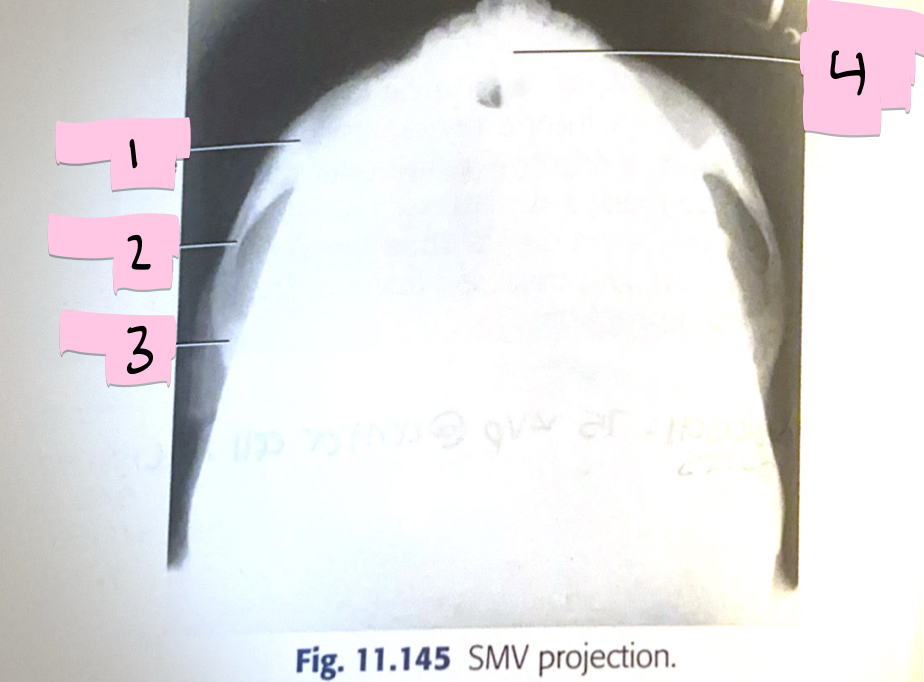

What is 1 pointing to?

Zygomatic bone

What is 2 pointing to?

Zygomatic arch

What is 3 pointing to?

Temporal bone

What is 4 pointing to?

Mandibular symphysis